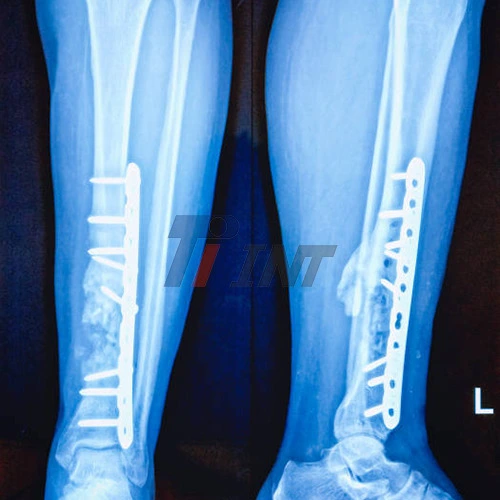

Titanium plates have become an indispensable tool in orthopedic surgery, particularly for leg injuries. These biocompatible devices are designed to provide stability and support to fractured bones, allowing them to heal properly. The use of a titanium plate in leg surgeries has numerous benefits:

- Osseointegration: Titanium has the unique ability to integrate with bone tissue, promoting a stronger connection between the plate and the bone.

The execution of titanium plate in leg surgeries has drastically made strides in persistent results, permitting speedier recuperation times and decreased complications. Specialists can presently address complex breaks and distortions with more prominent exactness, much obliged to the flexibility and unwavering quality of titanium inserts.

- X-rays to assess bone healing and plate positioning